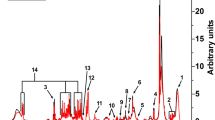

GABA can be detected in multiple forms in various human tissues. For example, the measurement of total CSF GABA detects several forms of GABA including “free GABA,” homocarnosine, 2-pyrrolidinone, and small amounts of other GABA-containing peptides (Fig. 1). In fact, homocarnosine and 2-pyrrolidinone are the major components of CSF, exceeding the amount of free GABA by more than 1,000-fold (Grove et al. 1982; Haegele et al. 1987). Homocarnosine is a dipeptide of GABA and histidine that is synthesized from GABA. 2-pyrrolidinone is the lactam of GABA, and while it is more abundant in CSF than GABA, it readily converts to GABA in the brain. Brain concentrations of homocarnosine and 2-pyrrolidinone are low with the human occipital lobe showing 2-pyrrolidinone concentrations half that of free GABA (Hyder et al. 1999; Kish et al. 1979). Moreover, intravenous infusion (Callery et al. 1979) or chronic oral administration (Fasolato et al. 1988) results in elevations of GABA in the brain from the conversion of 2-pyrrolidinone into free GABA.

2-Pyrrolidinone is elevated in ABAT deficiency. (a) Citric acid cycle, GABA shunt, and GABA metabolites: 2-pyrrolidinone and homocarnosine. (b) 2-Pyrrolidinone measured in Subject 1 plasma and Subject 2 plasma, urine, and CSF. (c) 2-Pyrrolidinone measured in plasma in Subject 2 before (“S2 pre”) and during treatment (“S2 post”) with flumazenil

Metabolomics screening showed abnormalities in both patients. Subject 1 had metabolomics screening conducted on plasma when he was 5 years and was not receiving flumazenil treatment. This testing showed 2-pyrrolidinone elevated more than 2 standard deviations (SD) above normal (z-score = 3.7) (Fig. 1b). Similarly, at age 1 year, Subject 2 had metabolomics screening in plasma, urine, and CSF all of which showed 2-pyrrolidinone elevated above normal (z-score = 6.1, 4.24, and 7.1) (Fig. 1b). Glutamate, which is just prior to GABA in the GABA shunt, was normal in all samples, as was alpha-ketoglutarate, which is just prior to glutamate and the metabolite that flows from the citric acid cycle to the GABA shunt (Fig. 1). Succinic semialdehyde, which is the product of GABA-T catabolism of GABA in the GABA shunt, was not measured. However, metabolites of the Kreb’s cycle that are just post GABA shunt were in the normal range: succinate, fumarate, and malate.

Subject 2 currently receives treatment for ABAT deficiency of flumazenil, 1.7 mg/kg/day. He was 2 years old at the time of initiation of treatment and was able to make significant gains in alertness, developmental milestones, and some amelioration of oculomotor apraxia. Metabolomics was conducted on patient plasma while the child was receiving treatment and the same elevation in 2-pyrrolidinone was observed (Fig. 1c). This reconciles with the mechanism of action of flumazenil as a GABA receptor antagonist that would not be expected to decrease the levels of GABA or its metabolites.

We observed elevated GABA in the brain of Subject 1 while also observing elevated 2-pyrrolidinone in this subject’s plasma. Similarly, Subject 2 showed elevated GABA in CSF (brain was not measured) and plasma alongside elevated 2-pyrrolidinone in both of these tissues. Notably, treatment with flumazenil did not appreciably reduce levels of 2-pyrrolidinone in Subject 2, which is in accordance with its mechanism of action as a negative allosteric modulator of GABA receptor rather than an agent of GABA degradation.

Lundgren and Hankins first suggested 2-pyrrolidinone as a “transport form” of GABA in 1978 (Lundgren and Hankins 1978) and subsequent work supports this theory. 2-pyrrolidinone crosses the blood–brain barrier more readily than GABA. 2-pyrrolidinone is more stable in plasma (Fasolato et al. 1988; Nakamura et al. 1991) and CSF (Grove et al. 1982; Haegele et al. 1987) than GABA, while readily converting to free GABA in the brain (Callery et al. 1979; Fasolato et al. 1988) where GABA exerts its neuromodulatory effects. 2-pyrrolidinone has been shown to have anticonvulsant properties (Sasaki et al. 1991) which may be a result of its conversion to GABA. Additionally, Vigabatrin, an irreversible inhibitor of ABAT, has been demonstrated to elevate CSF and brain GABA, homocarnosine, and pyrrolidinone (Hyder et al. 1999; Petroff et al. 1996; Petroff and Rothman 1998; Riekkinen et al. 1989; Rothman et al. 1997).

These studies support what we observed in our ABAT deficiency patients and we conclude that 2-pyrrolidinone is an excellent biomarker for GABA in plasma, urine, and CSF. As a biomarker for GABA, 2-pyrrolidinone would be a relevant metabolite to assess in individuals suspected of having a genetic disorder resulting in GABA elevations, such as ABAT deficiency or SSADHD, or individuals taking therapeutic interventions that would be expected to elevate GABA, such as Vigabatrin. The ability to distinguish between genetic and other causes of GABA/2-pyrrolidinone elevations would require the integration of genetic and metabolic testing.